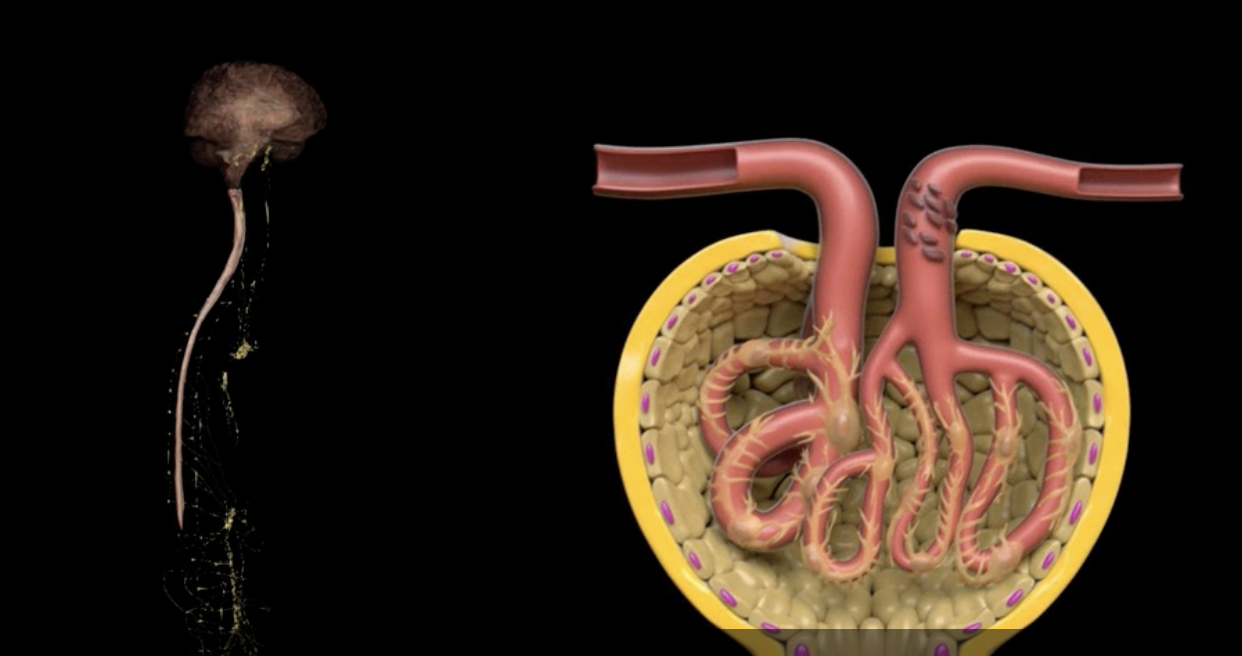

yellow: cortical nephron

blue: juxtamedullary nephron

yellow:

blue:

afferent arteriole

yellow

glomerulus

green

efferent arteriole

purple

orange: peritubular capillaries

green: vasa recta

efferent arteriole give rise to orange and green